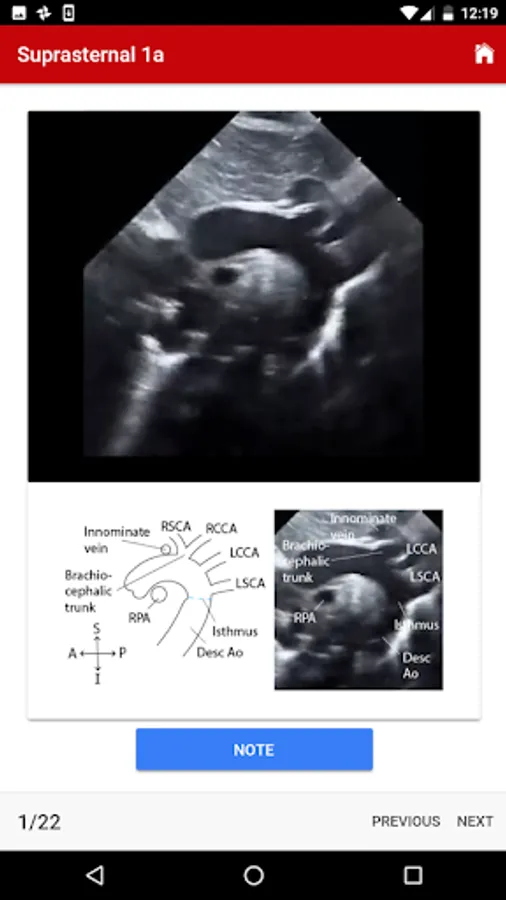

4. Suprasternal

The exact images and the order in which the images and views are obtained varies by institution. Each protocol (subcostal, parasternal, apical or suprasternal) can be followed in order by clicking on the next tab at the bottom of the page or you can click on an individual numbered view within the protocol list to be taken directly to that view. The name of the view and instructions will pop-up automatically at the bottom of the page. The instructions and additional notes can also be found in the “NOTE” button at the bottom of the page.